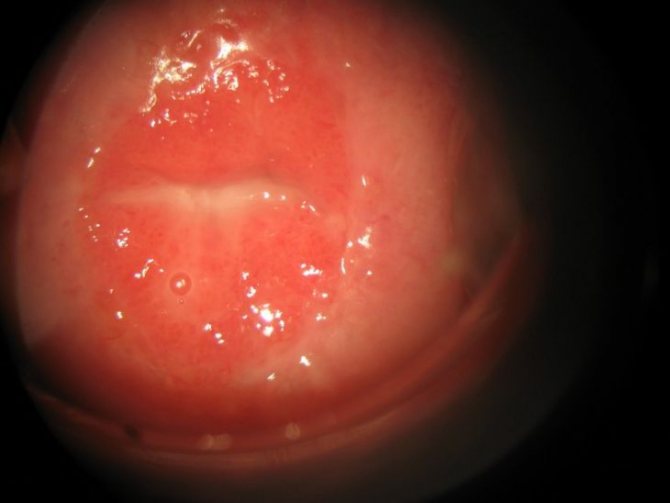

Помимо количественных, наблюдаются качественные нарушения – а именно процессы гиперкератоза (чрезмерного ороговения). Также описываемое заболевание называют «ковровой» лейкоплакией, так как при оптическом увеличении слизистая оболочка полости рта напоминает ворс ковра. Но такие изменения можно увидеть только при изучении пораженной слизистой под микроскопом. В свою очередь, усиленное размножение наблюдается по той причине, что вирус, размножаясь, не подавляет клетки, в которых он поселился, а наоборот стимулирует их.

При волосатой лейкоплакии наблюдается диспластический процесс – нарушение строения тканей из-за:

- чрезмерного размножения клеток;

- их скопления.

Из клеток формируются маленькие множественные выросты, которые и составляют морфологическую основу волосатой лейкоплакии.